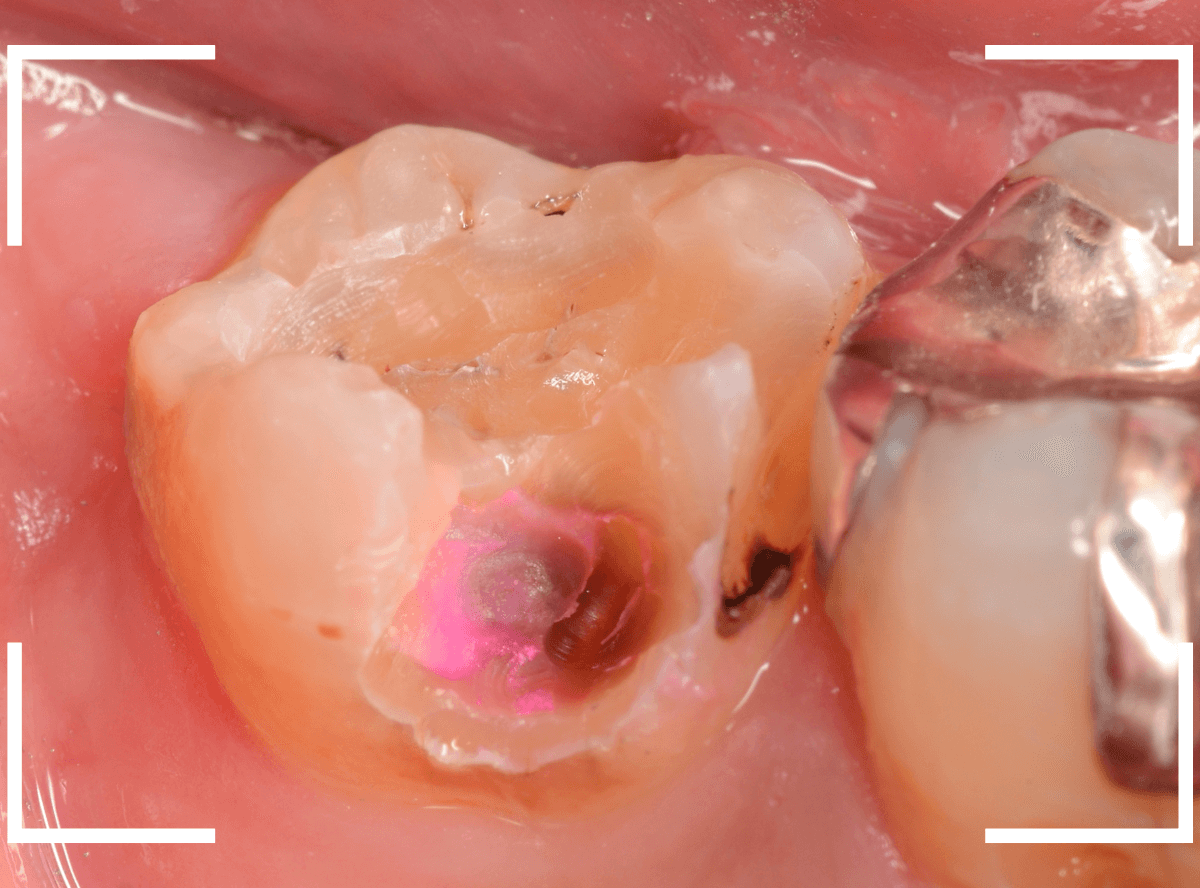

Case.17 レントゲンにはっきり写らないレジンの中の虫歯を削って調べる2

今回も、下の奥歯の虫歯を治療した例です。

特に症状はありませんが、以前に治療したレジンが劣化してすり減っているのと、少し中が黒く透けて見えて、虫歯になっているのが怪しいです。

青いラインが歯の神経です。

以前の虫歯が深めだったようで、レジンが深めにつめてあるのがわかります。

その下がうっすらと虫歯っぽい影になっています(赤いライン)。

虫歯になっているか微妙なラインですが、レジンも劣化していますので、患者さんにご説明して治療することになりました。

レントゲンで虫歯と思われる部分をレジンを除去しました。

見た目には虫歯かどうかはっきりわかりません。

う蝕検知液で染め出します。

うっすらと赤く染色されました。

レントゲン写真と同じく、レジンの下で静かに虫歯が進行し始めていたようです。

もともと深めの虫歯だった部分なので、早いうちに治療が進められてよかったです。

全てのレジンと虫歯を除去しました。

お薬をつめて、症状が出ないかしばらく経過観察します。

歯の外壁部分も薄くなってますので、レジンでは長期保存は難しいと思われます。

今回は、インレーで最終修復する予定です。